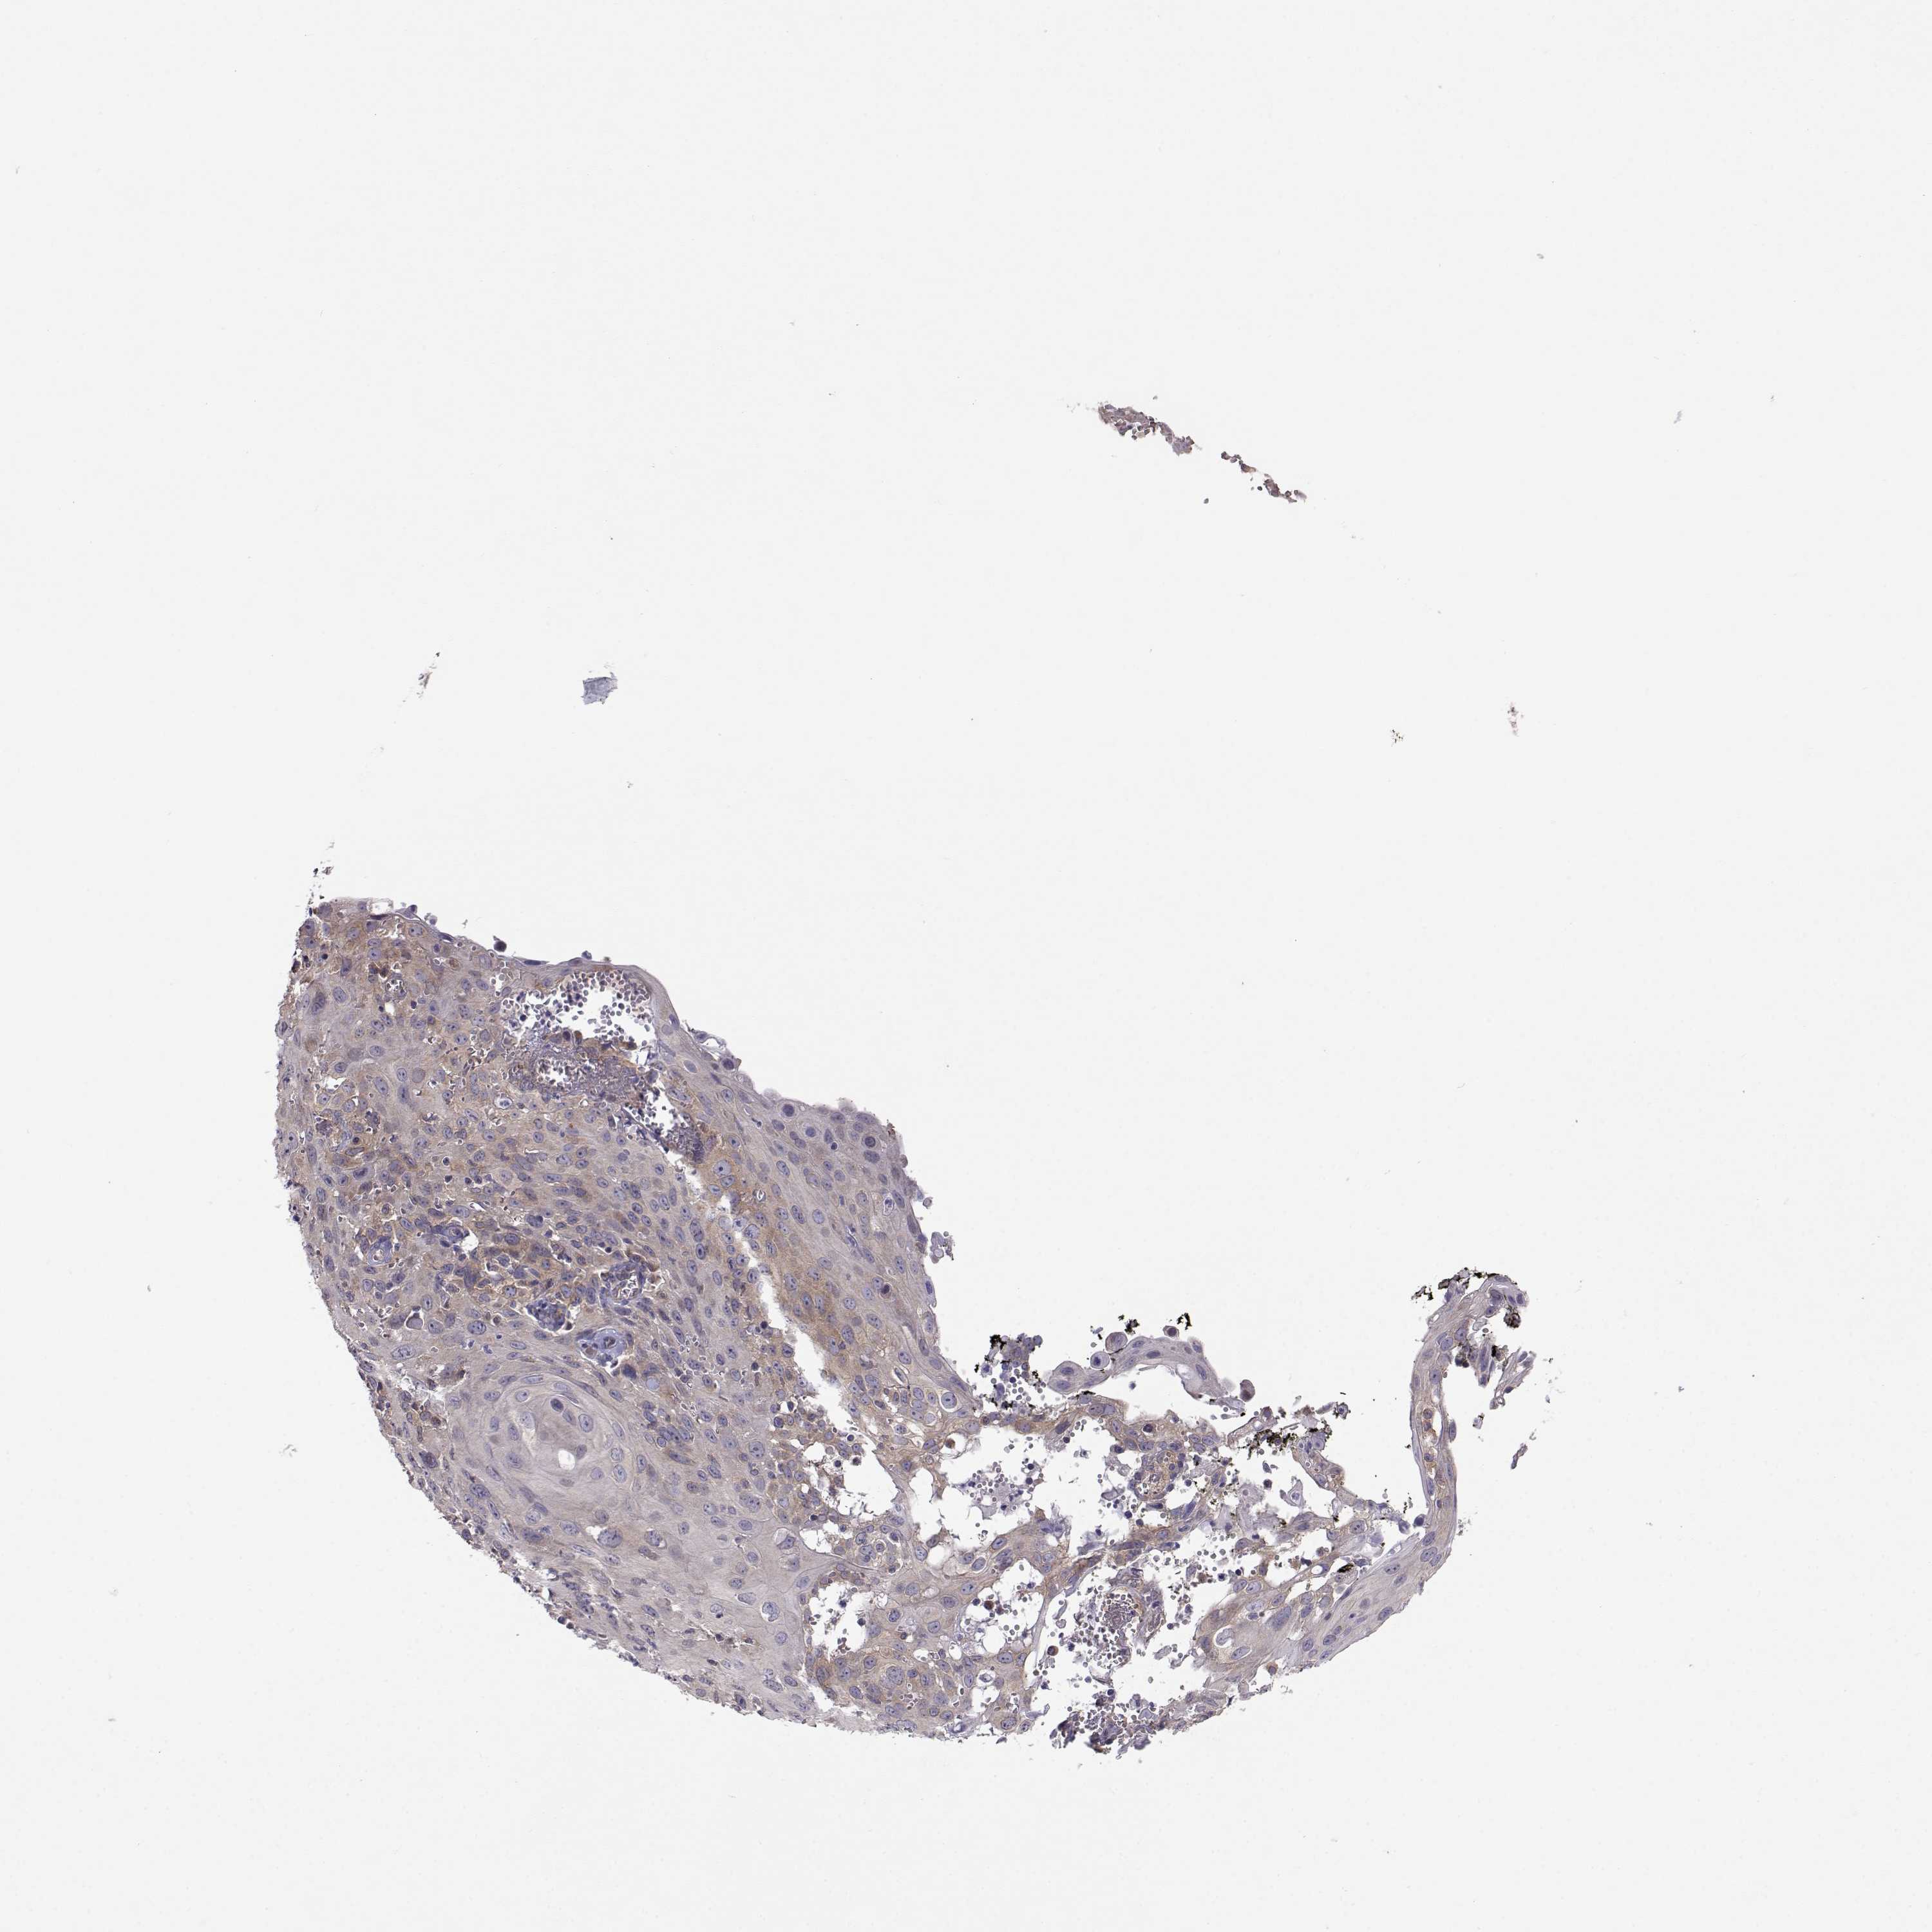

CERVICAL CANCER - Protein expressioni

A mouse-over function shows sample information and annotation data. Click on an image to view it in a full screen mode. Samples can be filtered based on level of antibody staining by selecting one or several of the following categories: high, medium, low and not detected. The assay and annotation is described here.

Note that samples used for immunohistochemistry by the Human Protein Atlas do not correspond to samples in the TCGA dataset.

Antibody stainingi

Antibody staining in the annotated cell types in the current human tissue is reported as not detected, low, medium, or high, based on conventional immunohistochemistry profiling in selected tissues. This score is based on the combination of the staining intensity and fraction of stained cells.

Each image is clickable and will lead to virtual microscopy that enables deeper exploration of all samples and also displays staining intensity scores, fraction scores and subcellular localization as well as patient and tissue information for each sample.

Antibody HPA073653

Staining

High

Medium

Low

Not detected

Intensity

Strong

Moderate

Weak

Negative

Quantity

>75%

75%-25%

<25%

None

Location

Nuclear

Cytoplasmic/membranous

Cytoplasmic/membranous,nuclear

Squamous cell carcinoma, NOS

Adenocarcinoma, NOS